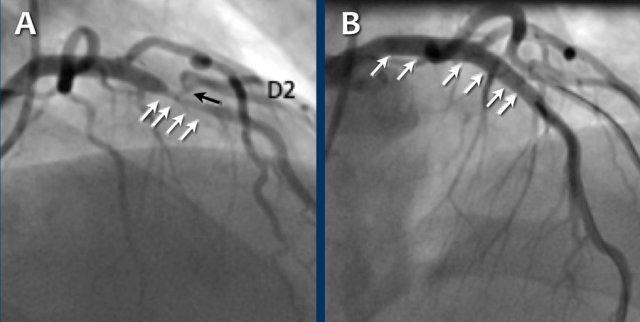

Continue with the next images of the same patient…

Same patient.

Double-oblique (A) and volume-rendered (B) images of the LAD showing the

location and the length of the plaque.

Also, the stenosis in the D2 branch of the LAD can be appreciated on the volume

rendered reconstruction.

Due to the degree of stenosis and the presence of napkin-ring sign (visible on

axial images) this patient underwent ICA where the presence of severe stenosis

was confirmed.

Continue with the next images…

A: ICA correlates with CTA and shows an 80% stenosis in the mid LAD

(white arrows) and a 60% stenosis in the D2 branch (black arrows). The D2

stenosis was overestimated on CTA.

B: PCI was performed during which a drug eluting stent (DES) was

implanted with good results (white arrows).